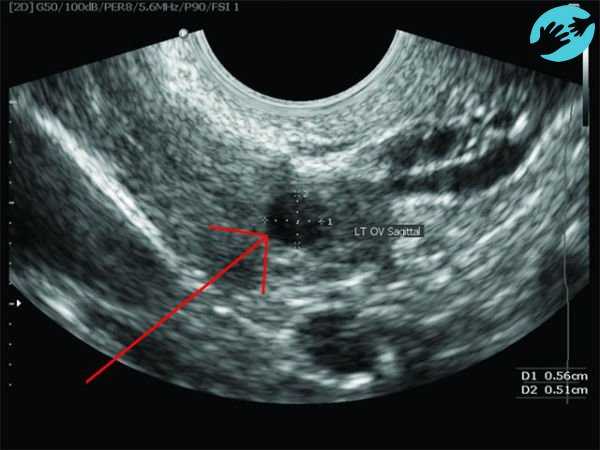

Поскольку в этой ситуации методы выявления точного дня, указанные выше не актуальны, то подтвердить свои расчеты можно другими способами. Наиболее достоверным будет УЗИ. Врач наблюдается за ростом фолликула, начиная через 5-9 дней после менструации. По скорости его роста и по содержанию гормона, он определит дату овуляции заблаговременно.